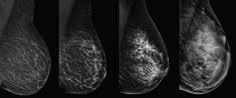

Gulf Islands Medical Imaging is excited to bring whole breast ultrasound screening to our community. Are you doing everything you can for your breast health? Did you know that for 50% of women, mammography alone may not be enough? Knowing your breast density is crucial, as additional screenings have shown to be beneficial in the early detection of breast cancer in dense tissue.

By adding the ABUS 3-D ultrasound exam to your breast screening routine, you can enhance your chances of early detection without adding any additional radiation. This non-invasive exam requires no injections, making it a safe and comfortable choice.